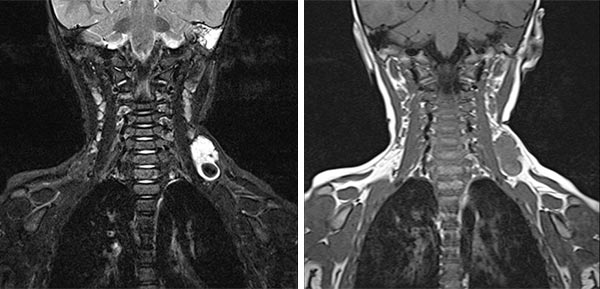

In coronal MRI (left image: T2-weighted, right image: non-enhanced T1-weighted), the venous malformation (VM) is very well delineated. It is strongly hyperintense in the T2 image, whereas it is isointense to the musculature in the non-enhanced T1 image. The signal intensity is typical of the character of a slow-flow lesion.

In coronal MRI (left: T2-weighted, right: T1-weighted non-enhanced) slightly more dorsally, a larger thrombus within the venous malformation is very well delineated. In the T2 image, this is hypointense compared to the severely hyperintense venous malformation. In the non-enhanced T1 image it is slightly more hyperintense than the surrounding hypointense venous malformation.